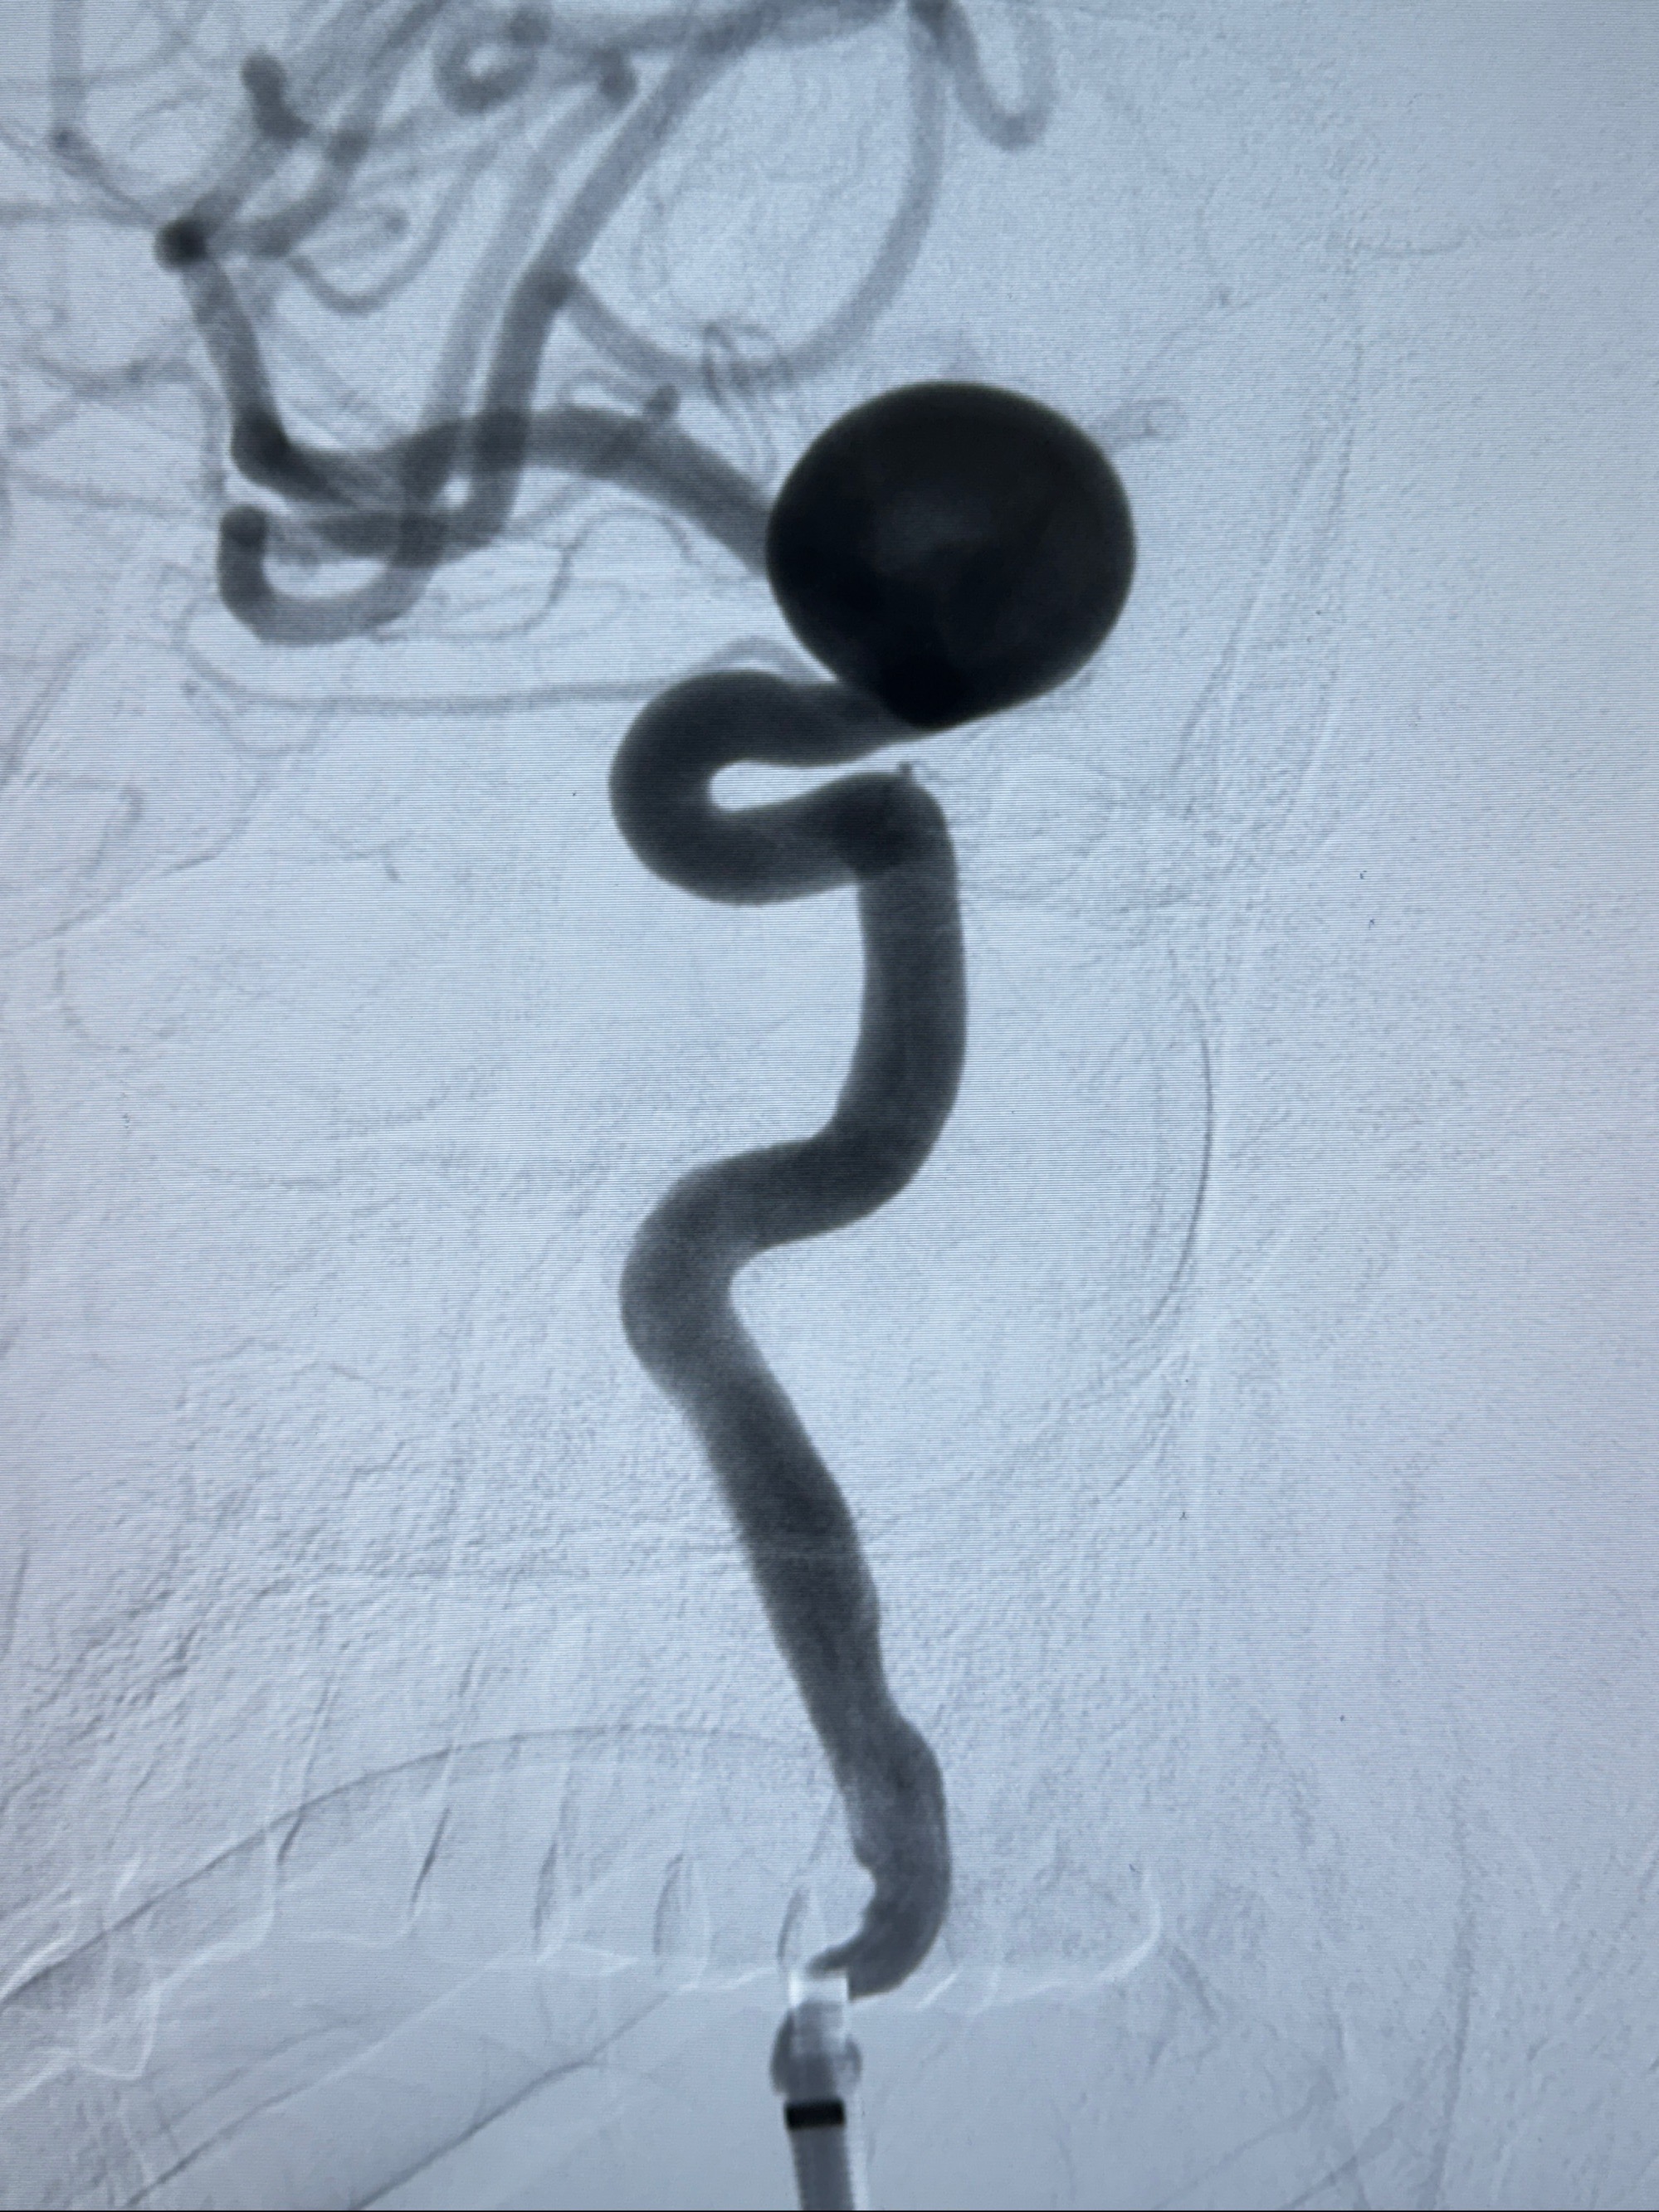

4.5-30mmTurbridge密网支架,于M1近心端打开

2024-01-08全麻下再行植入密网支架一枚

Tubridge 4.5-35mm

支架植入顺利,贴壁佳,支架内血流通畅,动脉瘤内血液滞留明显